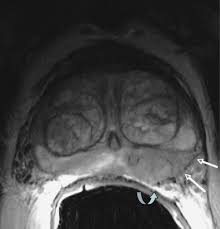

Pi Rads Prostate Imaging Reporting And Data System 2015 Version 2 European Urology

Pi Rads Prostate Imaging Reporting And Data System 2015 Version 2 European Urology from els-jbs-prod-cdn.jbs.elsevierhealth.com